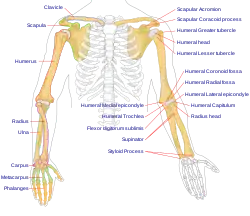

Anatomy - Biological engineering